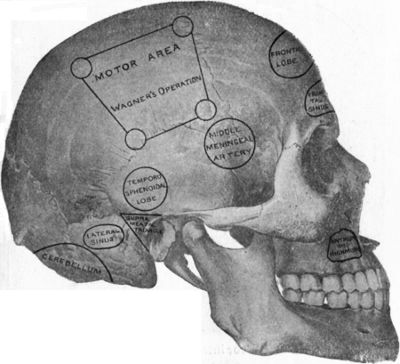

| 179. | Relations of the Motor and Sensory Areas to the Convolutions and to Chiene's Lines | 330 |

| 181. | Chiene's Method of Cerebral Localisation | 336 |

| 182. | To illustrate the Site of Various Operations on the Skull | 337 |

| 186. | Relations of the Middle Meningeal Artery and Lateral Sinus to the Surface as indicated by Chiene's Lines | 353 |